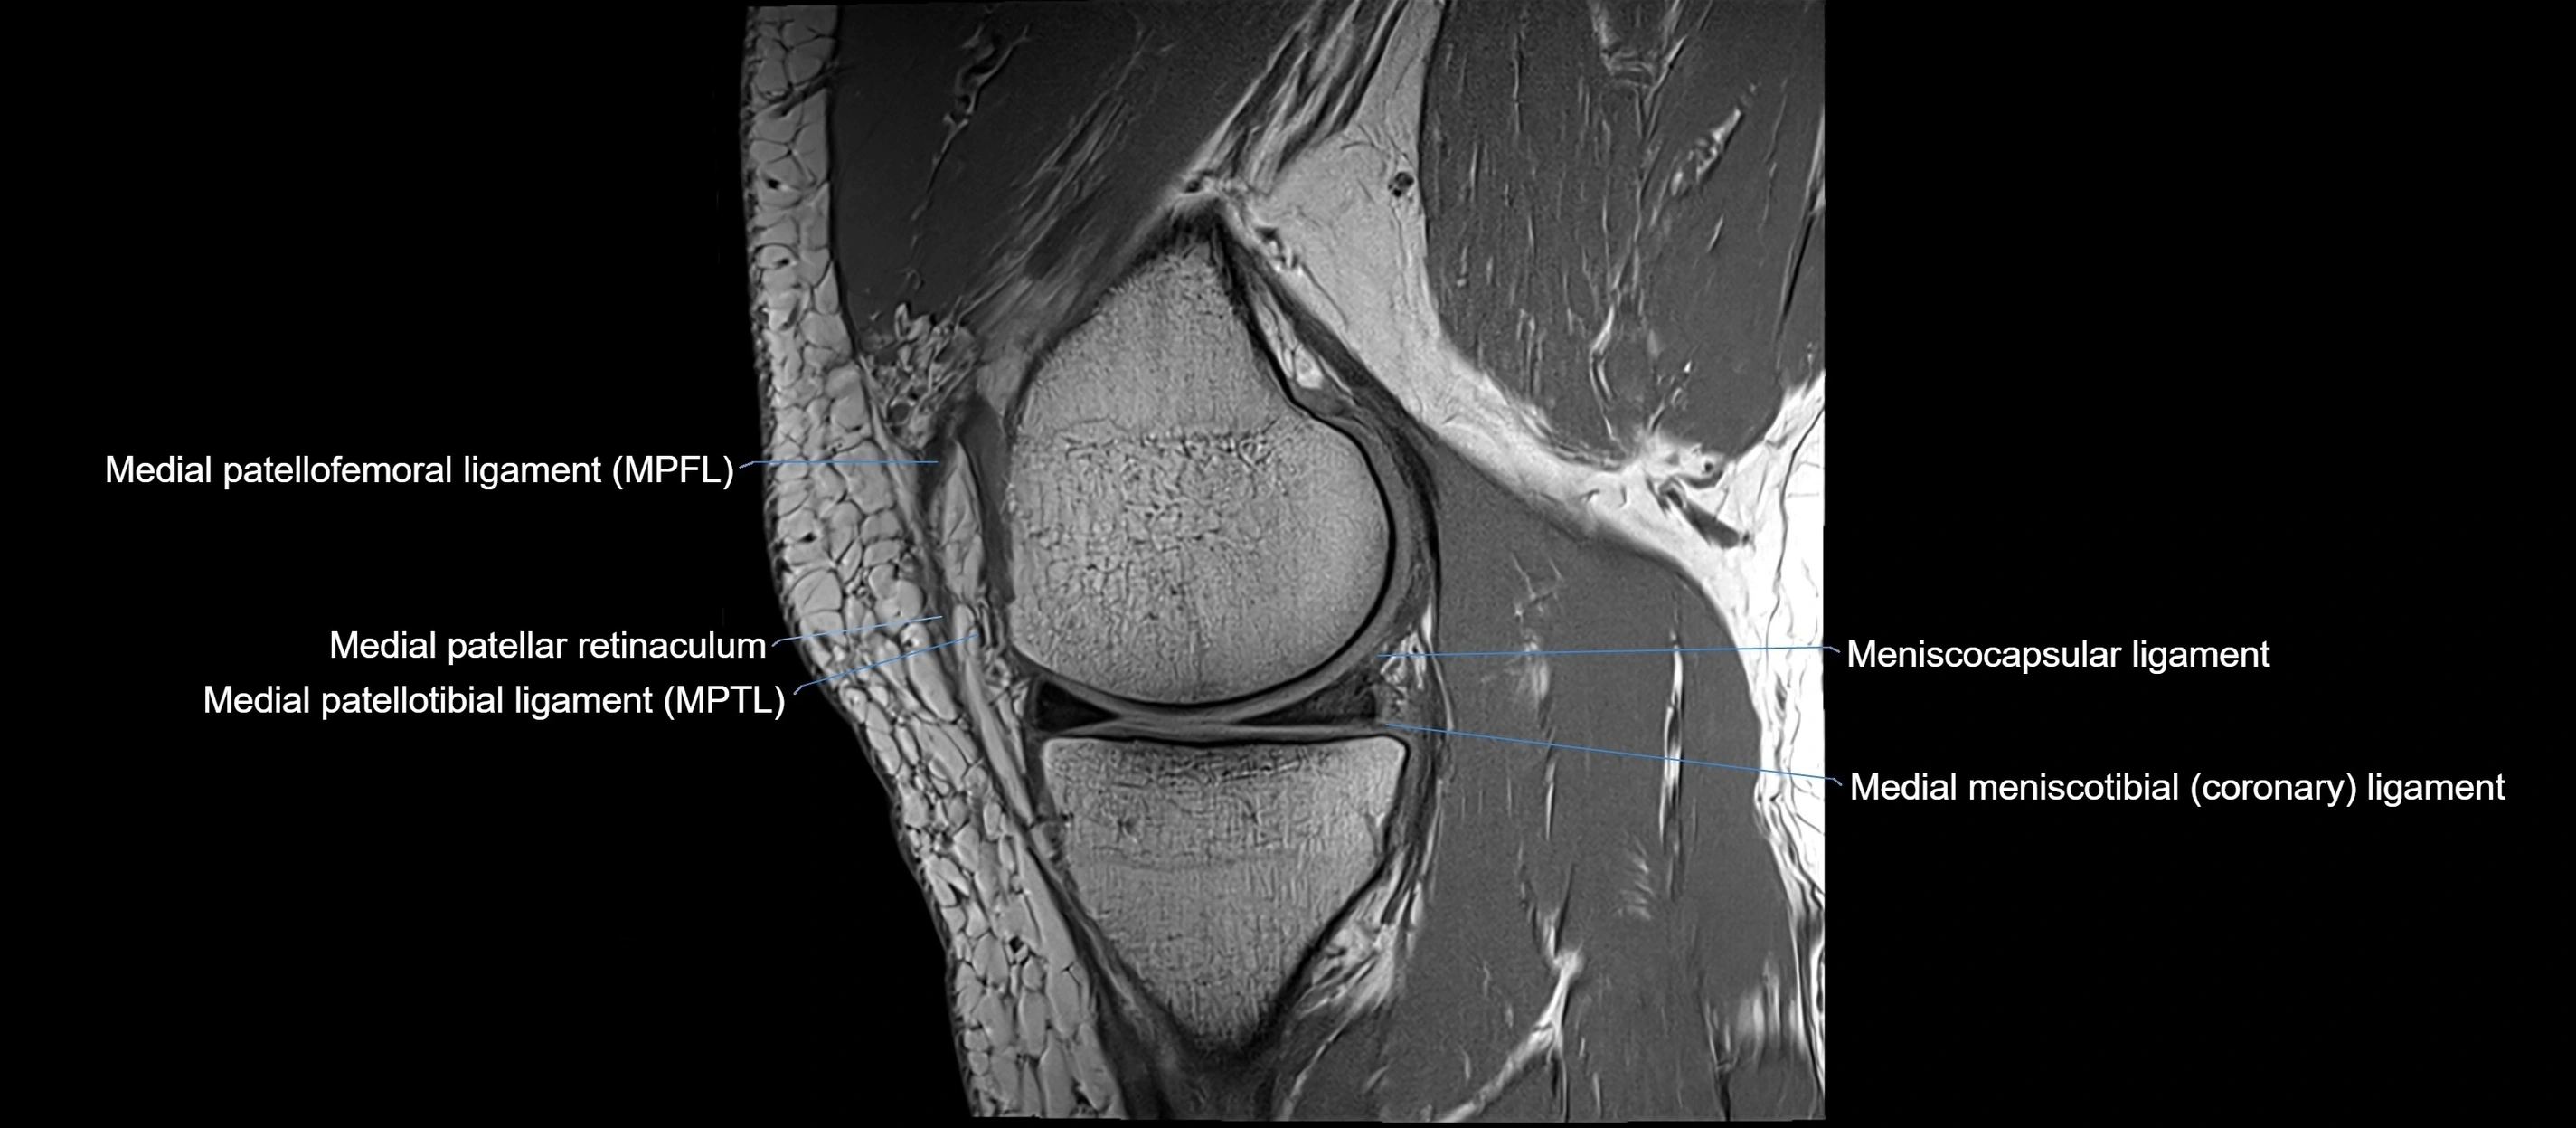

MRI images

image